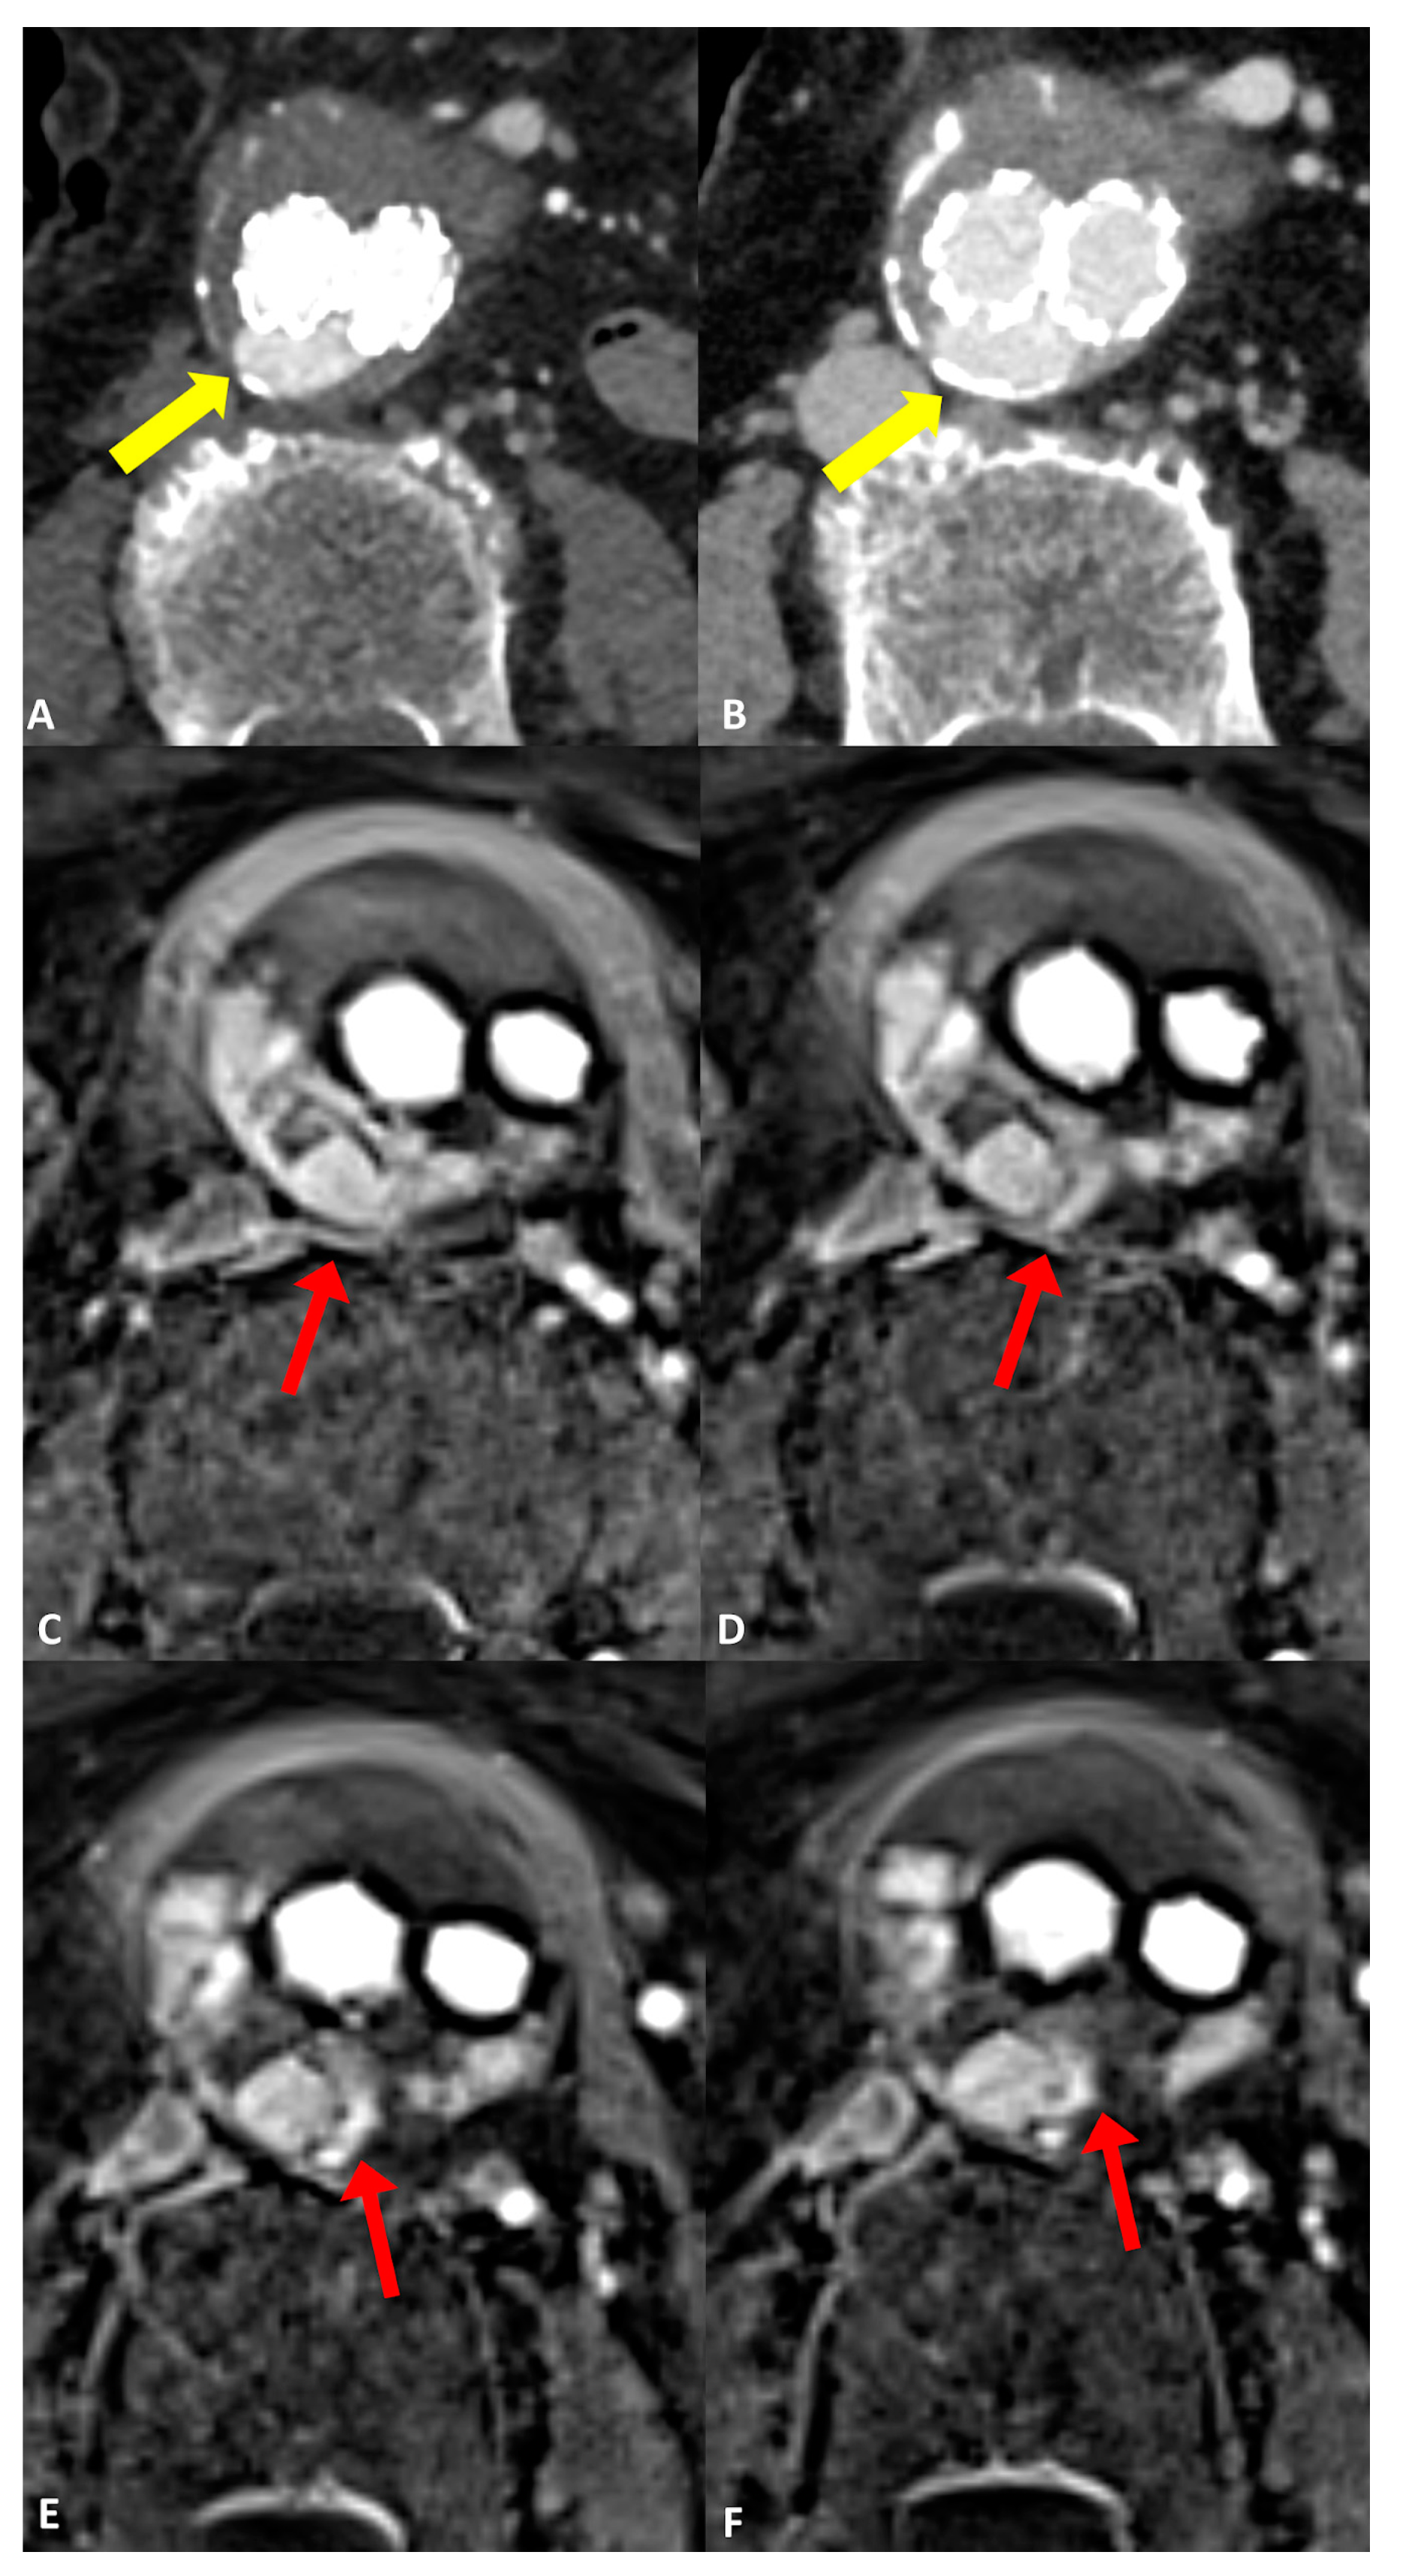

Figure 3.

Follow-up imaging after endovascular aortic aneurysm repair (EVAR) in a 79-year-old woman diagnosed with an infrarenal abdominal aortic aneurysm. Axial CT angiograms revealed an endoleak with inconclusive classification (type I, II, or III), marked by yellow arrows in (A) the post-contrast arterial phase and (B) the post-contrast delayed phase. (C–F) four consecutive axial slices utilizing the dynamic GRASP-VIBE sequence illustrated a communication between the right lumbar artery and the sac, highlighted by a red arrow in (C), followed by the entry of contrast material into the aneurysm sac and its distribution within, evident in (D–F) with red arrows. Notably, the contrast material displayed a similar signal to that of the right lumbar artery, which was less pronounced compared to the aorta/common iliac arteries. This observation favors the diagnosis of a type II endoleak originating from the right lumbar artery, as opposed to a graft defect.